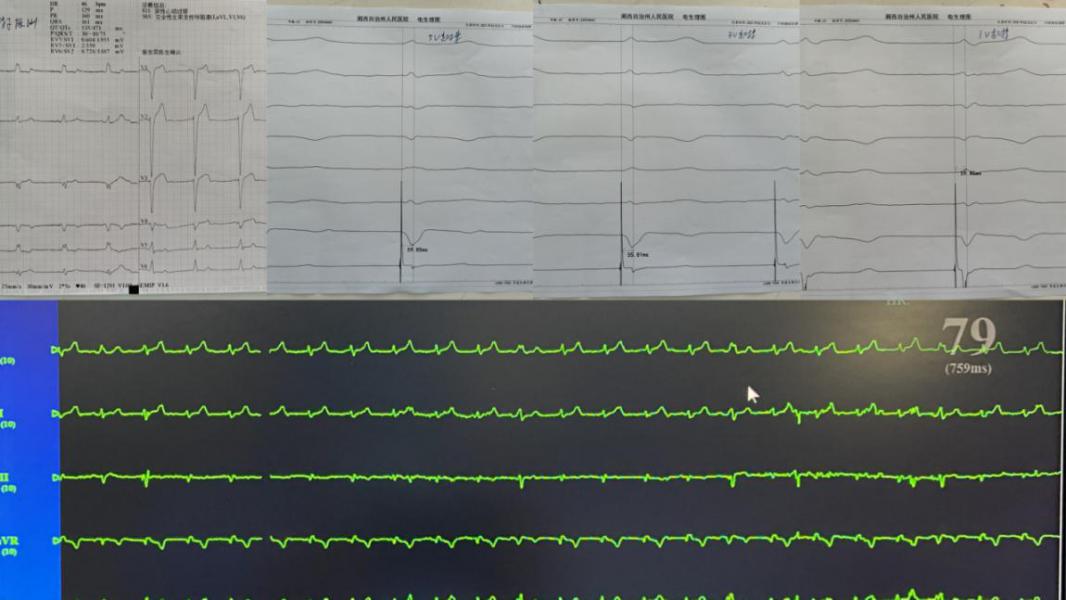

手术中,从右心室间隔侧将电极旋入左心室内膜下的左束支区域,成功实施了“左束支起搏”,左束支电位明显、术前心电图QRS波群从137ms变为术后心电图QRS波群106ms(QRS波群从宽到明显变窄),起搏各参数满意、电极固定牢固,手术圆满成功。